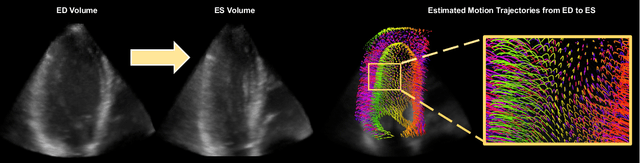

Abstract:Myocardial motion tracking stands as an essential clinical tool in the prevention and detection of Cardiovascular Diseases (CVDs), the foremost cause of death globally. However, current techniques suffer incomplete and inaccurate motion estimation of the myocardium both in spatial and temporal dimensions, hindering the early identification of myocardial dysfunction. In addressing these challenges, this paper introduces the Neural Cardiac Motion Field (NeuralCMF). NeuralCMF leverages the implicit neural representation (INR) to model the 3D structure and the comprehensive 6D forward/backward motion of the heart. This approach offers memory-efficient storage and continuous capability to query the precise shape and motion of the myocardium throughout the cardiac cycle at any specific point. Notably, NeuralCMF operates without the need for paired datasets, and its optimization is self-supervised through the physics knowledge priors both in space and time dimensions, ensuring compatibility with both 2D and 3D echocardiogram video inputs. Experimental validations across three representative datasets support the robustness and innovative nature of the NeuralCMF, marking significant advantages over existing state-of-the-arts in cardiac imaging and motion tracking.